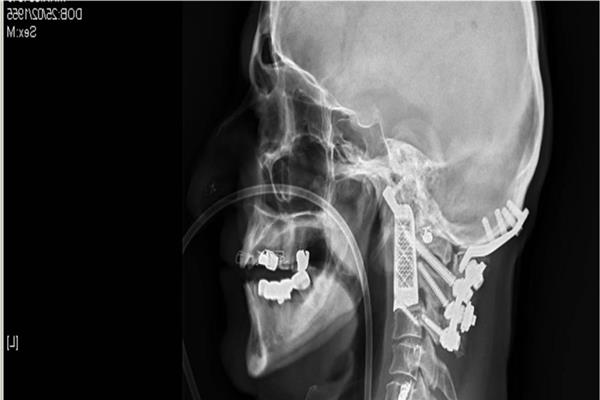

悉尼威爾士親王醫院的神經外科醫生,成功完成一例高難度的頸椎植入物手術。 患者的兩節頸椎由于受到腫瘤的影像需要被摘除,并更換為3D打印植入物。由于在手術中,醫生需要首先將病人的顱骨與脊髓組織分離,然后再通過植入物將他們重新連接起來。整個手術過程幾乎等于先將患者的頭部和身體分開,然后再連接上,手術風險可想而知。

面對一臺風險如此高的手術,醫生進行了周密的手術預規劃。***終確定的手術方案是從病人嘴部進入,切除腫瘤以及頭頸部的兩節脊椎,隨后植入鈦金屬3D打印脊椎。3D打印脊椎植入物是根據病人的身體和手術切除方案進行設計的,與進行過腫瘤和脊椎切除后的部位可以進行完美的匹配。者在術后的2個月中恢復順利。目前,他的脖子已經可以活動,再經過幾個月的恢復,飲食和語言功能也將逐漸恢復。

根據患者病情和醫生手術方案進行定制化設計的植入物,是此類手術成功的重要因素。這例手術中的脊椎植入物內部具有經過力學優化設計的晶格結構。金屬3D打印可以直接制造出這樣的復雜結構,并且在生產單件產品的成本方面也比傳統方式更低。